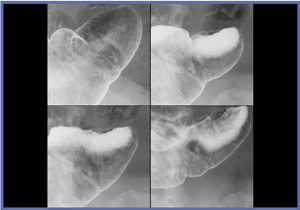

FPD装置1号機は,透視が見えにくい状態で撮影されたが,非常に精細な画像を得ることができた(図1,2)。偶然にも被検者が胃がんUc(表面陥凹)であったことも,評価を行う上で良い条件となった。1号機の評価は,非常にきれいに写るの一言に尽きる。透視が難しいことが大きな課題となっていたが,98年に現在の透視技術の完成に至った。

![]() 図1 FPD装置1号機の撮影像 わずかな表面陥凹が確認できる。 |

![]() 図2 FPD装置1号機の撮影像 アレアが喪失した部分が広がった表層拡大型胃がん |